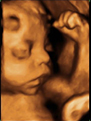

Ecografía Embarazo 4D - TERCER TRIMESTRE